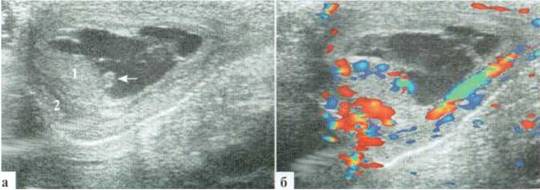

ПРАВОЕ ЯИЧКО — топография не изменена, размеры сохранены. Паренхима верхней части яичка сохранена, в нижней части имеется неправильной формы зона понижения эхогенности, аваскулярная при допплеровском исследовании. Сосудистый рисунок в остальных фрагментах яичка сохранен. Без эхопризнаков других структурных изменений на момент осмотра (рис. 2.3.15).

ЗАКЛЮЧЕНИЕ: эхопризнаки деструктивного орхита справа.

Рис. 2.3.15. Клинический пример № 10

Л ЕВОЕ ЯИЧКО - топография не изменена, размеры несколько больше контралатерального, преимущественно — в толщину. Паренхима яичка сохранена, без деструктивных изменений, с неравномерным понижением эхогенности. Сосудистый рисунок в паренхиме яичка усилен. Придаток значительно увеличен в размерах (22x15мм, на контралатеральной стороне — 12x5мм), гиперемирован при допплеровском исследовании. Определяется неизмененная гидатида размерами около 2x1мм (рис. 2.3.16). Эхопризнаки незначительного количества жидкостного компонента в оболочках, без интра- и паратестикулярных патологических включений на момент осмотра. Мягкие ткани левой половины мошонки значительно утолщены.

ЗАКЛЮЧЕНИЕ: эхопризнаки орхоэпидидимита слева.

Рис. 2.3.16. Клинический пример № 11:

1 - яичко, 2 — придаток, 3 — выпот;

а — поперечный скан по средней линии мошонки с визуализацией медиальных отделов обоих яичек: определяется значительное усиление интратестикулярного сосудистого рисунка слева;

б, в — продольный скан левой половины мошонки в В-режиме и цветовом допплеровском режиме соответственно. Паренхима яичка имеет «мозаичную» структуру с неравномерным понижением эхогенности. Интратестикулярный сосудистый рисунок значительно усилен, придаток гиперемирован. Неизмененная гидатида малых размеров показана стрелкой